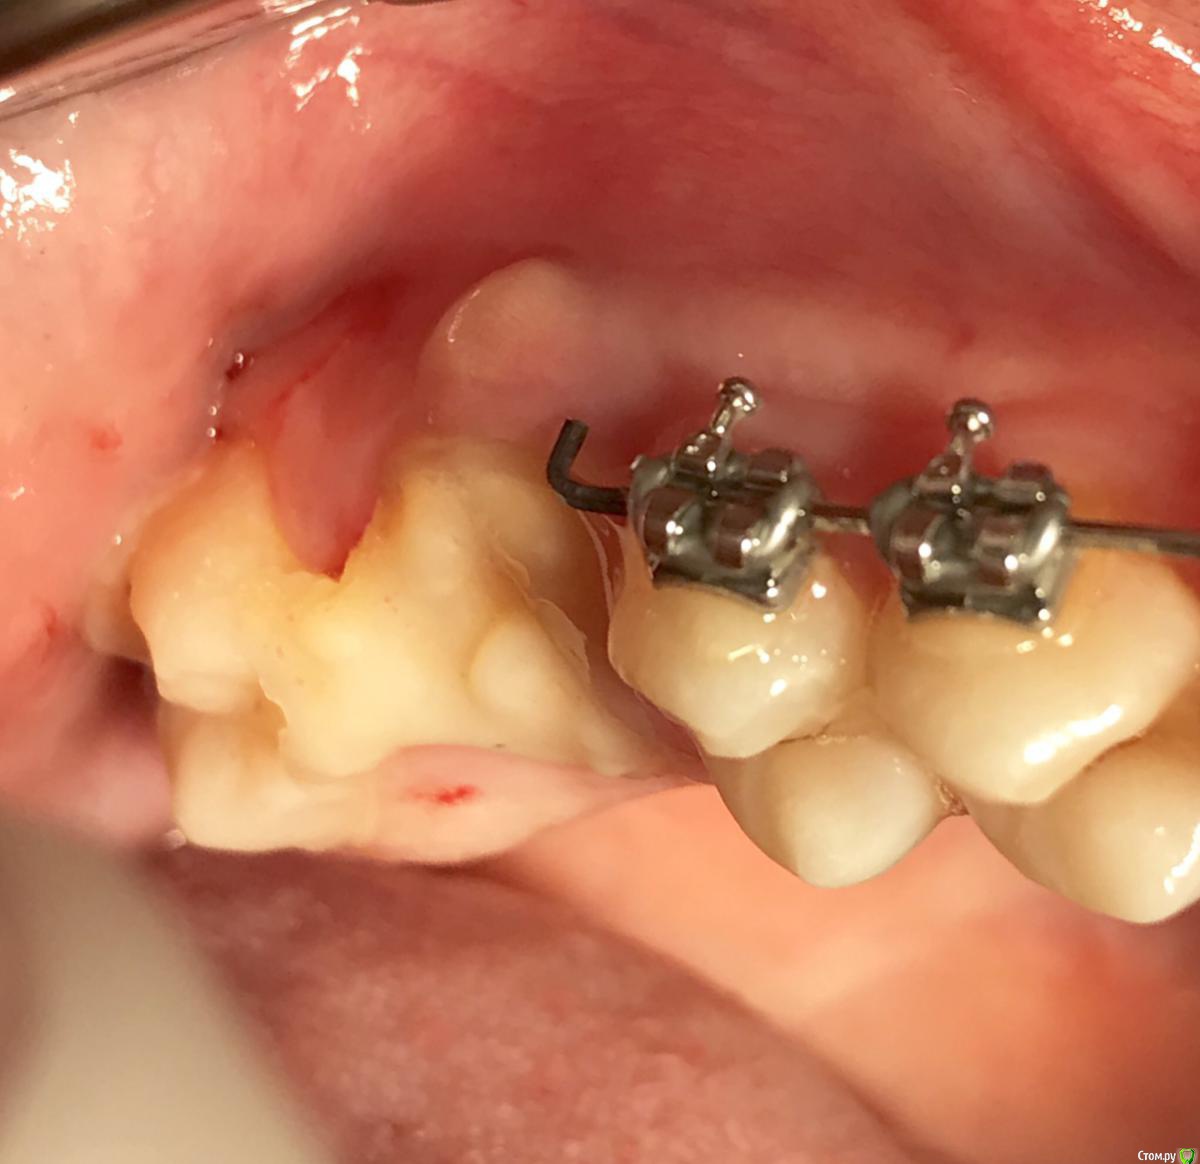

Nazim_NV86 Опубликовано 31 мая, 2018 Поделиться Опубликовано 31 мая, 2018 (изменено) У меня 2 вопроса:1. Что это на дне лунки на первом скрине?2. Что смущает вас на последнем скрине? Я правильно понимаю, туда же надо закрутиться ? Там больше кости и не выросло бы гипотетически. Изменено 31 мая, 2018 пользователем Nazim_NV86 Ссылка на комментарий

kamranchick Опубликовано 31 мая, 2018 Поделиться Опубликовано 31 мая, 2018 У меня 2 вопроса:1. Что это на дне лунки на первом скрине?2. Что смущает вас на последнем скрине? Я правильно понимаю, туда же надо закрутиться ? Там больше кости и не выросло бы гипотетически.1 какули - пломбировочный материал, никак не мог до него дотянутся2, ну да, туда закрутиться, ну я не хотел больше, хотел чтобы хотя бы тот обьем и остался, а в итоге имеем приличную атрофию Ссылка на комментарий

Kazankov.Egor Опубликовано 4 июня, 2018 Поделиться Опубликовано 4 июня, 2018 Пробки намертво приклеены.Причина не знаю в чем(Это провал, ибо пациент готовится на имплантацию уже.Тут даже 3.5 с трудом проходитна контрольке нет перелома вестибулярной стенки? Ссылка на комментарий

kamranchick Опубликовано 7 июня, 2018 Поделиться Опубликовано 7 июня, 2018 я честно говоря не уловил о чем вы тут ))Я удалил атравматично зубы, сделал пробки и плотно зафиксировал их в лунке, в надежде что останется много чего, но после повторного кт, видим атрофию, да довольно серьезную, в чем оишбка, либо так и должно бьыть Ссылка на комментарий

kamranchick Опубликовано 5 июля, 2018 Поделиться Опубликовано 5 июля, 2018 Короче методика крайне дискутабельная. в плане ортовытяжения еще рабочая метода, но как сохранения костной ткани...... Ссылка на комментарий

Bier Опубликовано 5 июля, 2018 Автор Поделиться Опубликовано 5 июля, 2018 Пообщался с Ромой Новиченко, он сказал, что в таких ситуациях с тонкой-тонкой кортикальной пластинкой нужно "пробку" делать больше, чтобы она заходила немного апикальнее вестибулярного костного края. Ссылка на комментарий

kamranchick Опубликовано 5 июля, 2018 Поделиться Опубликовано 5 июля, 2018 Пообщался с Ромой Новиченко, он сказал, что в таких ситуациях с тонкой-тонкой кортикальной пластинкой нужно "пробку" делать больше, чтобы она заходила немного апикальнее вестибулярного костного края.я даже пол корня оставлял, у меня кость ушла, а десны было вагон, выложу чуть позже кт Ссылка на комментарий